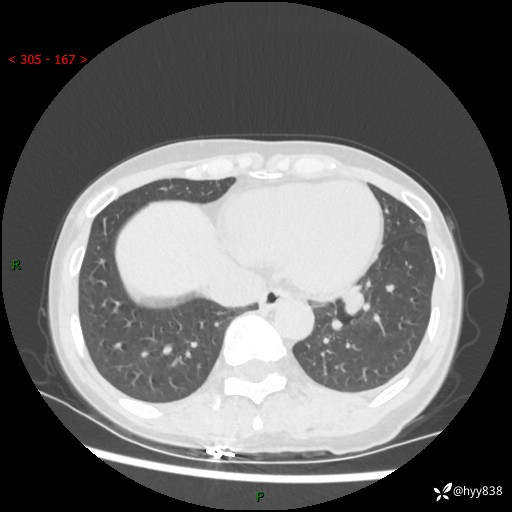

【患者信息】:55岁/女

【主诉】:咳嗽咳痰半月,发现肺占位2天

【现病史及既往史】:患者半月前出现咳嗽咳痰,伴头晕胸闷、无发热气喘。于当地医院住院行抗感染治疗1周(具体药物不详),后咳嗽减轻,但仍未完全缓解,复查胸部CT示:左肺下叶1.8*1.2结节软组织影。为求进一步诊治来我院,门诊以“肺占位”收入院。 自患病以来,精神、饮食、睡眠尚可,大小便正常,体力体重无明显减少。

【检查】:胸部CT平扫+增强

各期CT值:40hu 57hu 49hu